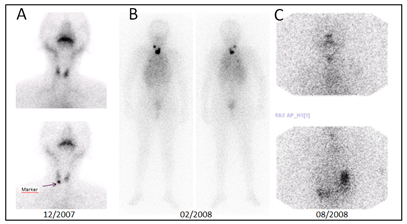

Thyroid Scintigraphy (3/12/07) revealed an area of hypofunction in the lower pole of the right lobe (palpable nodule) (Figure 1A).

Post-operative thyroid scintigraphy showed intense uptake in thyroid remnant and in thorax in a diffuse pattern suggesting lung metastasis (Figure 1B).

Chest X-ray: bilateral miliary seeding. CT: disseminated pulmonary nodules. Respiratory function: normal. Subsequent WBS (08/2008) showed residual thyroid gland. (Figure 1C) leading to a second therapeutic dose (130 mCi; 07/09/2009).

Figure 1